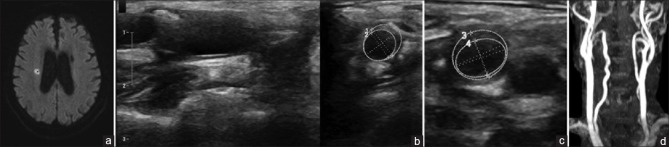

Abstract Image